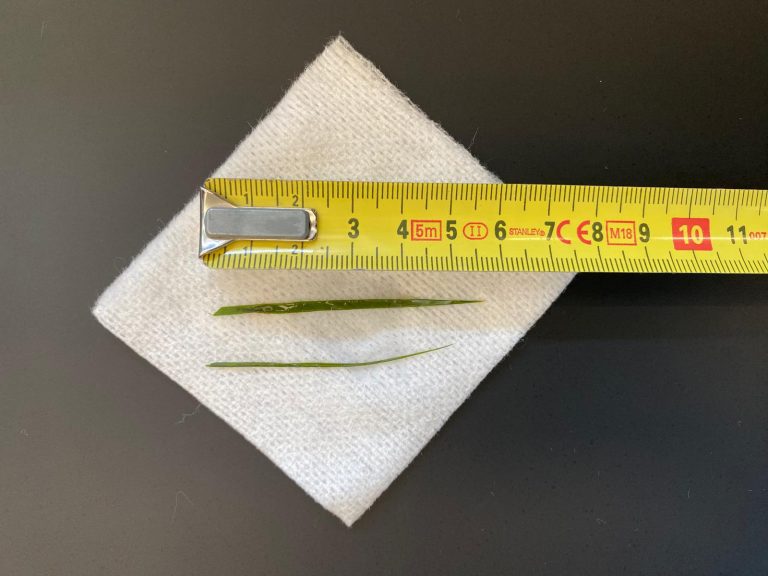

Tijdens de operatie leek het in eerste instantie niet te lukken om de steentjes terug te spoelen naar de blaas. Er werd meerdere keren gespoeld en pas toen we het al bijna wilden opgeven, kwamen eindelijk de steentjes los en konden ze naar de blaas gespoeld en hieruit verwijderd worden. Voor de zekerheid hebben we ze geteld. De blaas werd vervolgens nog enkele keren gespoeld en er werd meerdere keren gecontroleerd of de plasbuis echt goed doorlaatbaar was. Vervolgens werd de blaas gesloten. Ook de buikholte werd meerdere keren met warm fysiologische zoutoplossing gespoeld, om mogelijke lekkage van urine naar de buikholte te verdunnen, waarna de buik in 3 lagen gesloten werd. Browny mocht hierna lekker uitslapen in een verwarmd opnamehokje.